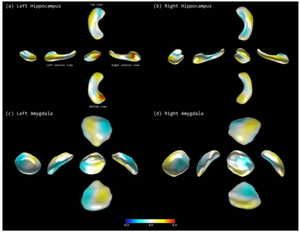

- 5.11 Individual subject classification of mixed dementia from pure subcortical vascular dementia based on subcortical shape analysis